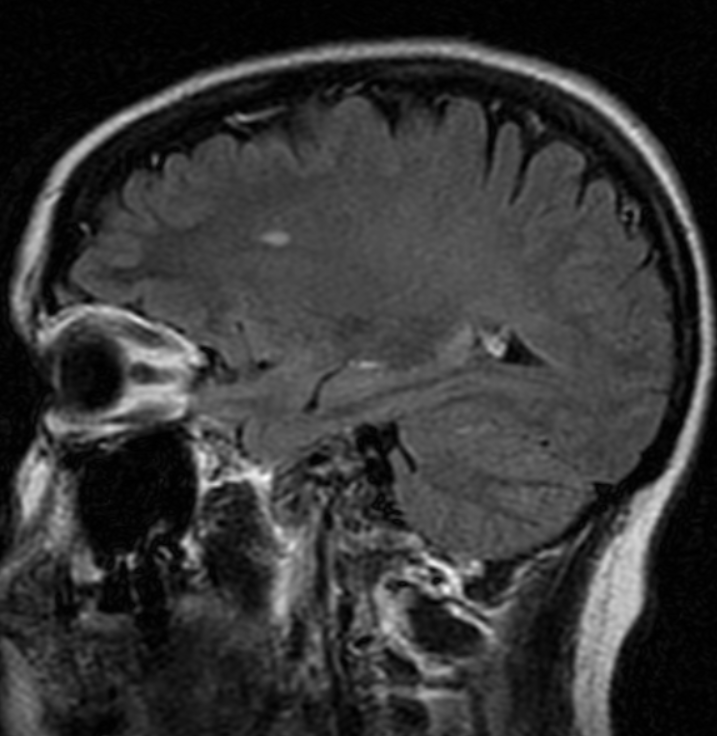

Иллюстрации и пояснения: гиподенсивный очаг на КТ головного мозга